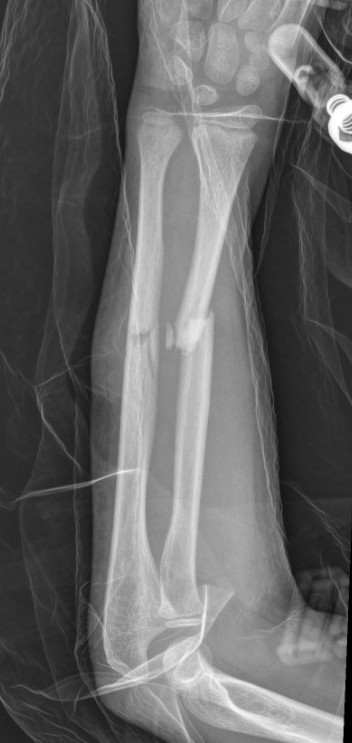

Complete

Greenstick

Buckle / torus

Single or both bone

Non Operative Management

Acceptable Position

< 10 years old: < 15 degrees malalignment

> 10 years old: < 10 degrees malalignment

< 1 - 2 years of growth remaining: Anatomic alignment required

Operative Management

Indications

Outside parameters for non-operative treatment (see above)

Loss of reduction

Options for displaced fractures

1. MUA

- young patients < 10

- greenstick fractures